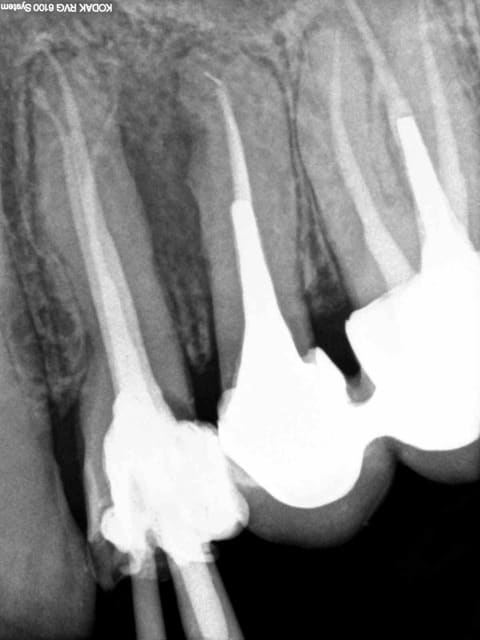

J'ai un de mes patients du cabinet où je travaillais avant qui m'a contacté car il a une reprise d'infection sous la CCM sur 46. Le praticien lui a déposé la couronne et va entreprendre le retraitement endodontique. Puis réaliser une nouvelle couronne. Etant donné que cela fait 3 ans que la couronne est posée le patient est mécontent. Il m'a appelé pour savoir s'il était possible d'avoir une indemnisation.

Je vous mets les photos en pièce jointe.

Ne leur dis surtout pas que tu as fait une faute. A la radio, ton obt est bonne.C'est tout.

Ton endo était pas mal.

C'est étonnant que le matériau d'obturation qui était dense en 2011 se soit dégradé à ce point et si vite.

Il est possible qu'il y ait autre chose (perfo latérale un peu en dessous du plancher, fracture de la racine MV).

Pour moi jusqu'à preuve du contraire c'est un alea.

Tu veux dire que, sur la radio, c'est à peu près blanc jusqu'au bout de la racine?

Parce que c'est tout ce qu'on peut dire sur cette endo. :-)))

Par contre à ta place je ne contesterais rien du tout, t'es en tort à 300%. J'espère pour toi que toutes tes endos ne sont pas comme ça. Certains me diront que je suis sévère blablabla "ça t'es jamais arrivé de rater" etc, mais en sortant de la fac faire ça je trouve ça honteux.

Mets au moins un cône un minimum calibré. La gutta ne "disparaît" pas.

Completement d'accord avec enlaye pour le multifactoriel ;l'infection est inter radiculaire , suite a une recession parodontale importante ,il suffit de voir la radio. Le retraitement (avec ou sans digue, :-)) est bien, mais ne donnera rien de plus!

Pour l'endo, c'est vrai que la disparition du matériaux d'obturation ne plaide pas en la faveur de notre jeune confrère.

La radio post-op du 15/11/2011 semble montrer la présence de cône de gutta dépassant coronairement . L'erreur ne viendrait-elle pas d'une empreinte de l'ic dans la foulée .

la préparation a retiré les cônes laissant le ciment endodontique.

Concernant une lésion interradiculaire je suis dubitatif en voyant uniquement cette radio .